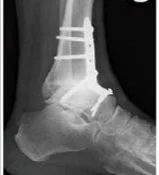

Ankle arthrodesis involves removing the remaining cartilage from the ankle joint and positioning the tibia and talus in optimal alignment. The bones are then secured together using plates, screws, or other fixation devices to allow them to fuse into a single, stable bone.